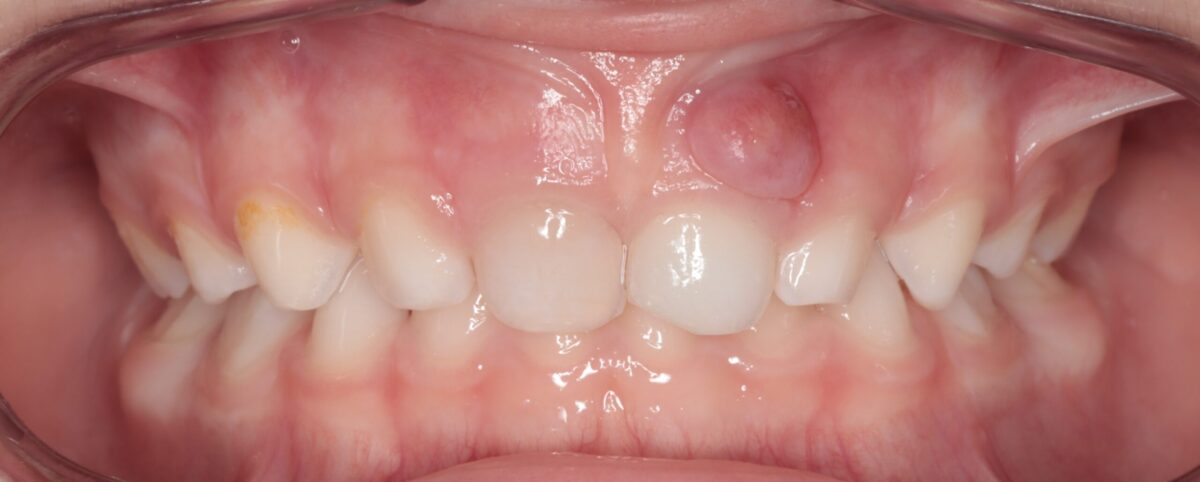

En ocasiones, el nervio del diente resulta dañado en el mismo momento del golpe (incluso a veces puede observarse un halo rosado interno en el diente por la pequeña hemorragia que se ha producido en su interior). En estos casos el tiempo que transcurre desde el traumatismo hasta la visita al Odontopediatra es vital y cualquier retraso juega en contra de la salvación del diente, por lo que debemos de acudir cuanto antes al odontopediatra, pues es importante salvar el diente, aunque sea de leche y más aun tratándose de un diente definitivo.